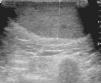

Presentaba un hematoma en la cara anterolateral externa de la pierna izquierda de 20cm. Un año antes había presentado un hematoma en la pierna derecha de 25 por 15cm que requirió drenaje quirúrgico y colocación de sistema de tratamiento de cierre asistido con vacío (fig. 2). Se realizó una ecografía que mostró un gran hematoma en la cara anterolateral de la pierna izquierda que se extendía desde la región poplítea hasta el tobillo y que asentaba, sobre todo, en el plano subcutáneo. La estructura tenía un espesor aproximado de 5cm (fig. 3). Se procedió al desbridamiento quirúrgico y posteriores curas tópicas, con reepitelización progresiva.